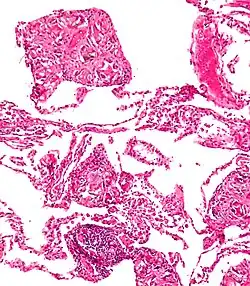

Both children and adults experience problems caused by foreign objects becoming lodged within their bodies. Young children, in particular, are naturally curious and may intentionally put shiny objects, such as coins or button batteries, into their mouths. They also like to insert objects into their ear canals and nostrils.[1] The severity of a foreign body can range from unconcerning to a life-threatening emergency. For example, a coin causes local pressure on the tissue but generally is not a medical emergency to remove. A button battery, which can be a very similar size to a coin, generates hydroxide ions at the anode and causes a chemical burn in two hours.[2] An ingested button battery that is stuck in the esophagus is a medical emergency. In 2009, Avolio Luigi and Martucciello Giuseppe showed that although ingested nonmagnetic foreign bodies are likely to be passed spontaneously without consequence, ingested magnets (magnetic toys) may attract each other through children's intestinal walls and cause severe damage, such as pressure necrosis, perforation, intestinal fistulas, volvulus, and obstruction.[3]

A coin seen on AP CXR in the esophagus

A coin seen on lateral CXR in the esophagus